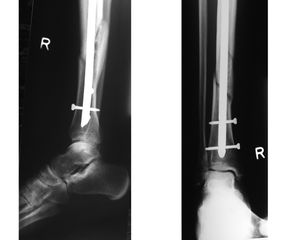

اكتشاف الكسور

ويستطيع الأطباء استكشاف الكسور بعدة طرق. فعادة يكون هناك ألم أو جرح، أو لين في منطقة الكسر. كما يكون هناك ورم في الأنسجةحول مكان الكسر وتغيُّر في اللون. وأحيانًا تتحرك العظمة تحت الجلد ويكون هناك تشوٌه ظاهر. ويدل صوت الطقطقة غالبًا على كسر في العظمة. والطقطقة صوت صرير خشن يحدث عندما تحتك نهايتا عظمة مكسورة بعضهما ببعض. ولكن هناك حالات لا يمكن فيها اكتشاف الكسر إلا باستخدام الأشعة السينية. وبصفة عامة،تلتئم الكسور البسيطة غير المصحوبة بخلع بسرعة،إذا تم تثبيتها في الجبس Plaster-of-Pairs أما الكسور المضاعفة والكسور المصحوبة بخلع، فتحتاج إلى علاج جراحي قبل وضع الجبس. ويجب أن يتوقف الجزء المكسور من الجسم عن الحركة حتى تتوفر المساعدة المتاحة.

- - تتوقف العملية الجراحية على نوع الكسر ، امكانيات الجراح العملية ، الامكانيات المتوفرة بحجرة العمليات .

- -العملية قد تكون بسيطة 1-2 براغي ،او DHS ، استبدال مفصل الورك THP .